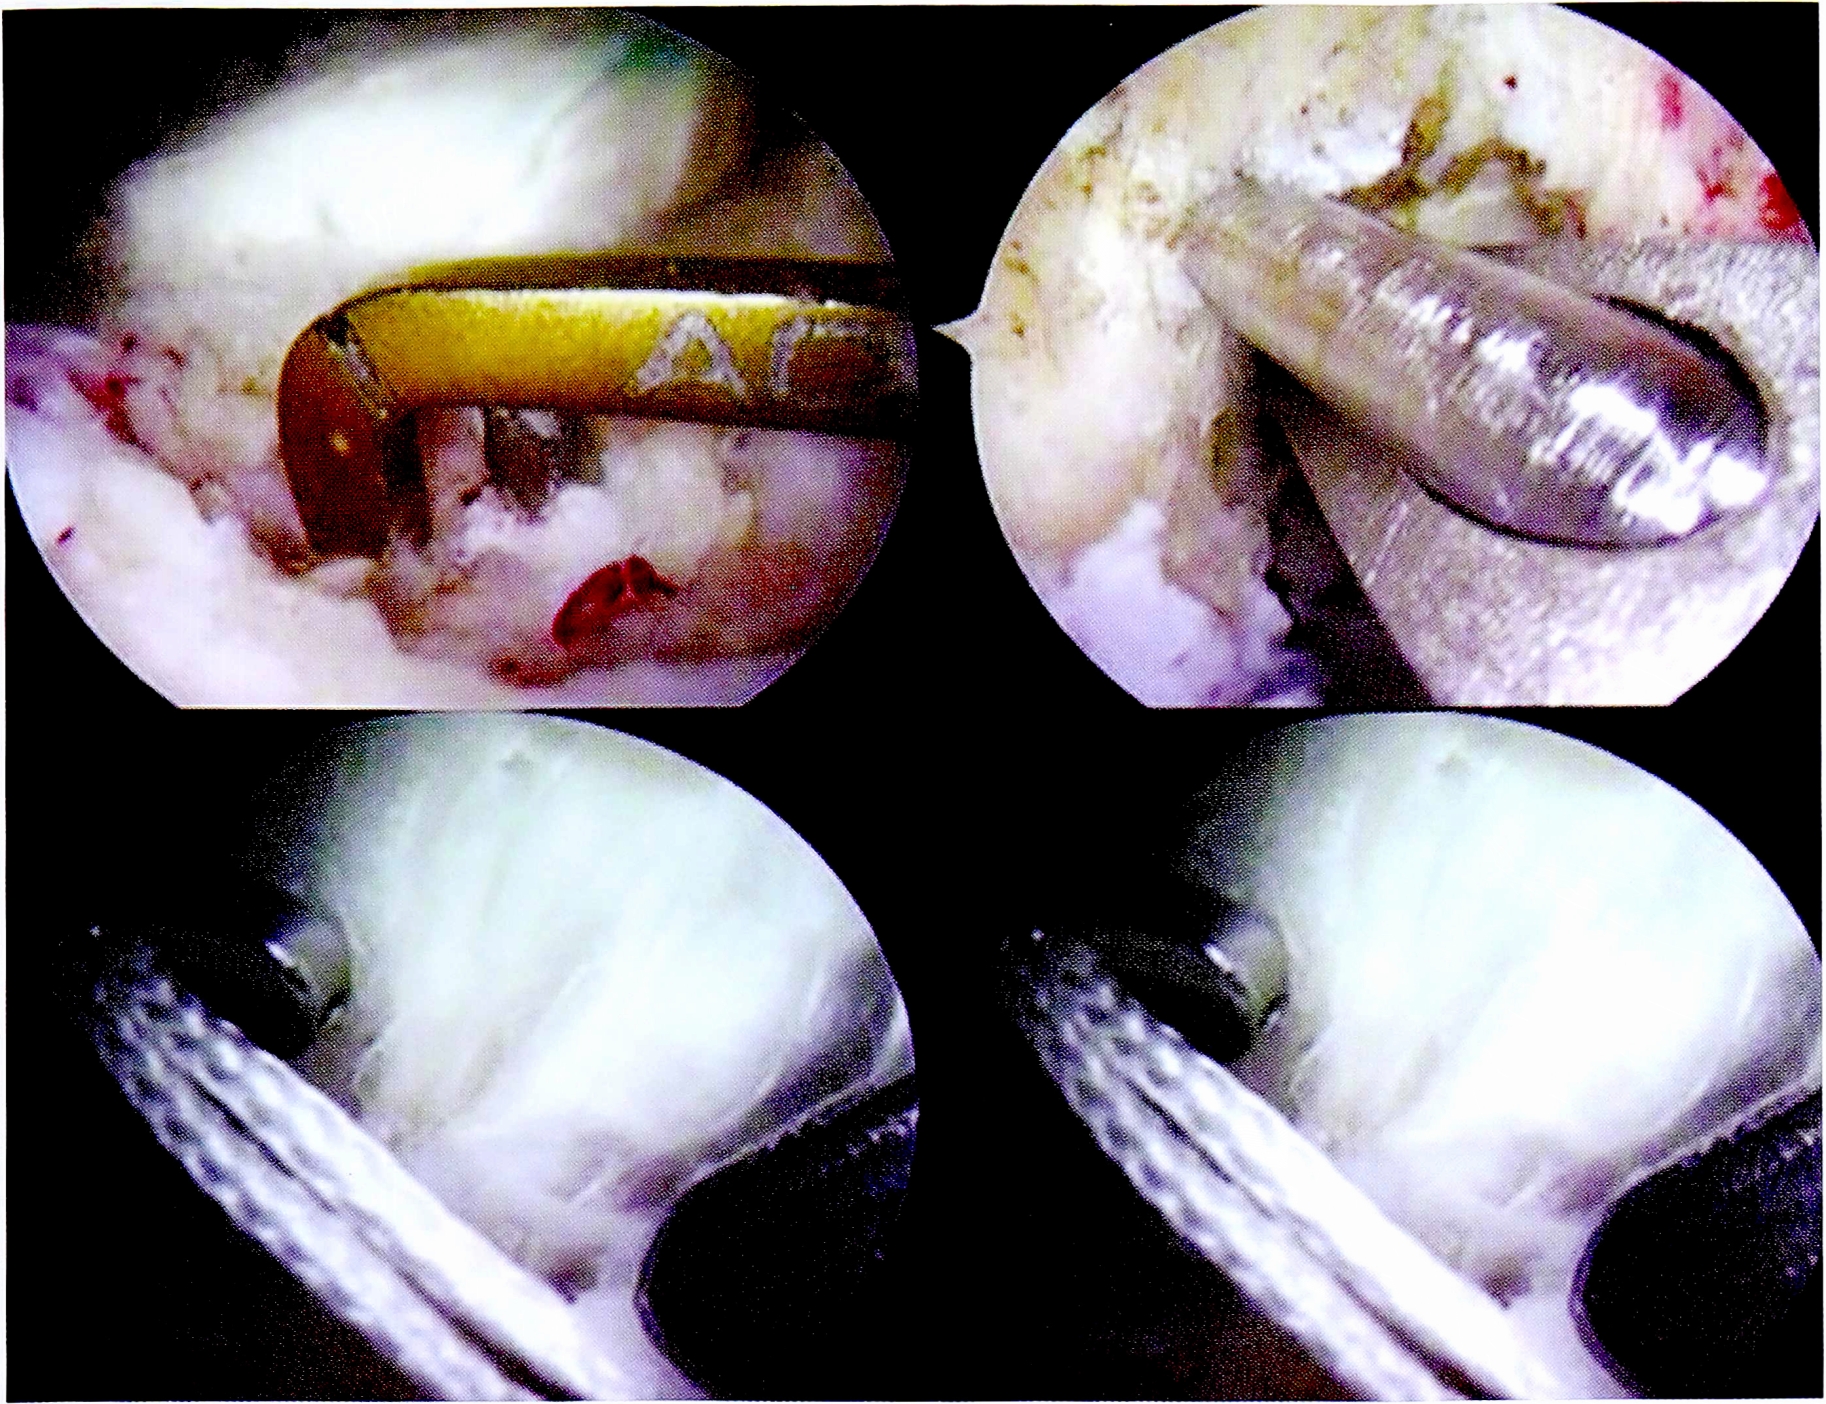

Перед операцией всем пациентам были выполнены МРТ коленного сустава (рис. 1) и рентгенография под нагрузкой (рис. 2). Результаты клинического осмотра, рентгенологических и MPT-исследований фиксировались согласно протоколу IKDC 2000. Для функциональной оценки коленного сустава были использованы опросники IKDC и Lisholm-Gillqist. Болевой синдром оценивался по визуальной аналоговой шкале (VAS).

Рис. 2. Рентгенография коленного сустава с нагрузкой для оценки степени заднего смещения голени.

Fig. 2. Functional X-ray to masure knee posterior instability.

Формирование костных тоннелей проводилось с использованием направителей из набора для пластики крестообразных связок. Костный тибиальный тоннель для ЗКС создавался согласно разработанной методике, через латеральный мыщелок, с выходом в зоне задней межмыщелковой ямки на 15 мм ниже щели сустава (рис. 4).

Рис. 4. Артроскопическая картина формирования тибиального костного тоннеля для пластики ЗКС.

Fig. 4. Making of tibial bone tunnel.

Бедренный костный тоннель формировали согласно анатомическому положению нативной ЗКС — в положении «1,5—2 ч» (для правого коленного сустава), на 3-4 мм кзади от заднего края хряща мыщелка бедренной кости (рис. 5).

Рис. 5. Артроскопическая картина формирования феморального костного тоннеля для пластики ЗКС.

Fig. 5. Making of femoral bone tunnel.

После проведения и фиксации на бедренной кости трансплантата ЗКС формировались костные тоннели для пластики ПКС. Использовались стандартная транстибиальная методика и набор направителей для ее выполнения (рис. 7).

Рис. 7. Артроскопическая картина основных этапов пластики ПКС.

Fig. 7. Main stages of ACL plasty.

Таким образом, костные тоннели в большеберцовой кости проводились через разноименные мыщелки: латеральный для ЗКС и медиальный для ПКС.

Следует отметить необходимость соблюдения строгой последовательности фиксации аллотрансплантатов в костных тоннелях. Авторами рекомендуется первым этапом выполнять натяжение и фиксацию в каналах трансплантата ЗКС, затем — трансплантата ПКС. Такая последовательность позволяет максимально вывести голень из заднего подвывиха. Последним этапом производится дополнительное натяжение фиксированных трансплантатов за счет самозатягивающихся петель фиксаторов в бедренных каналах.